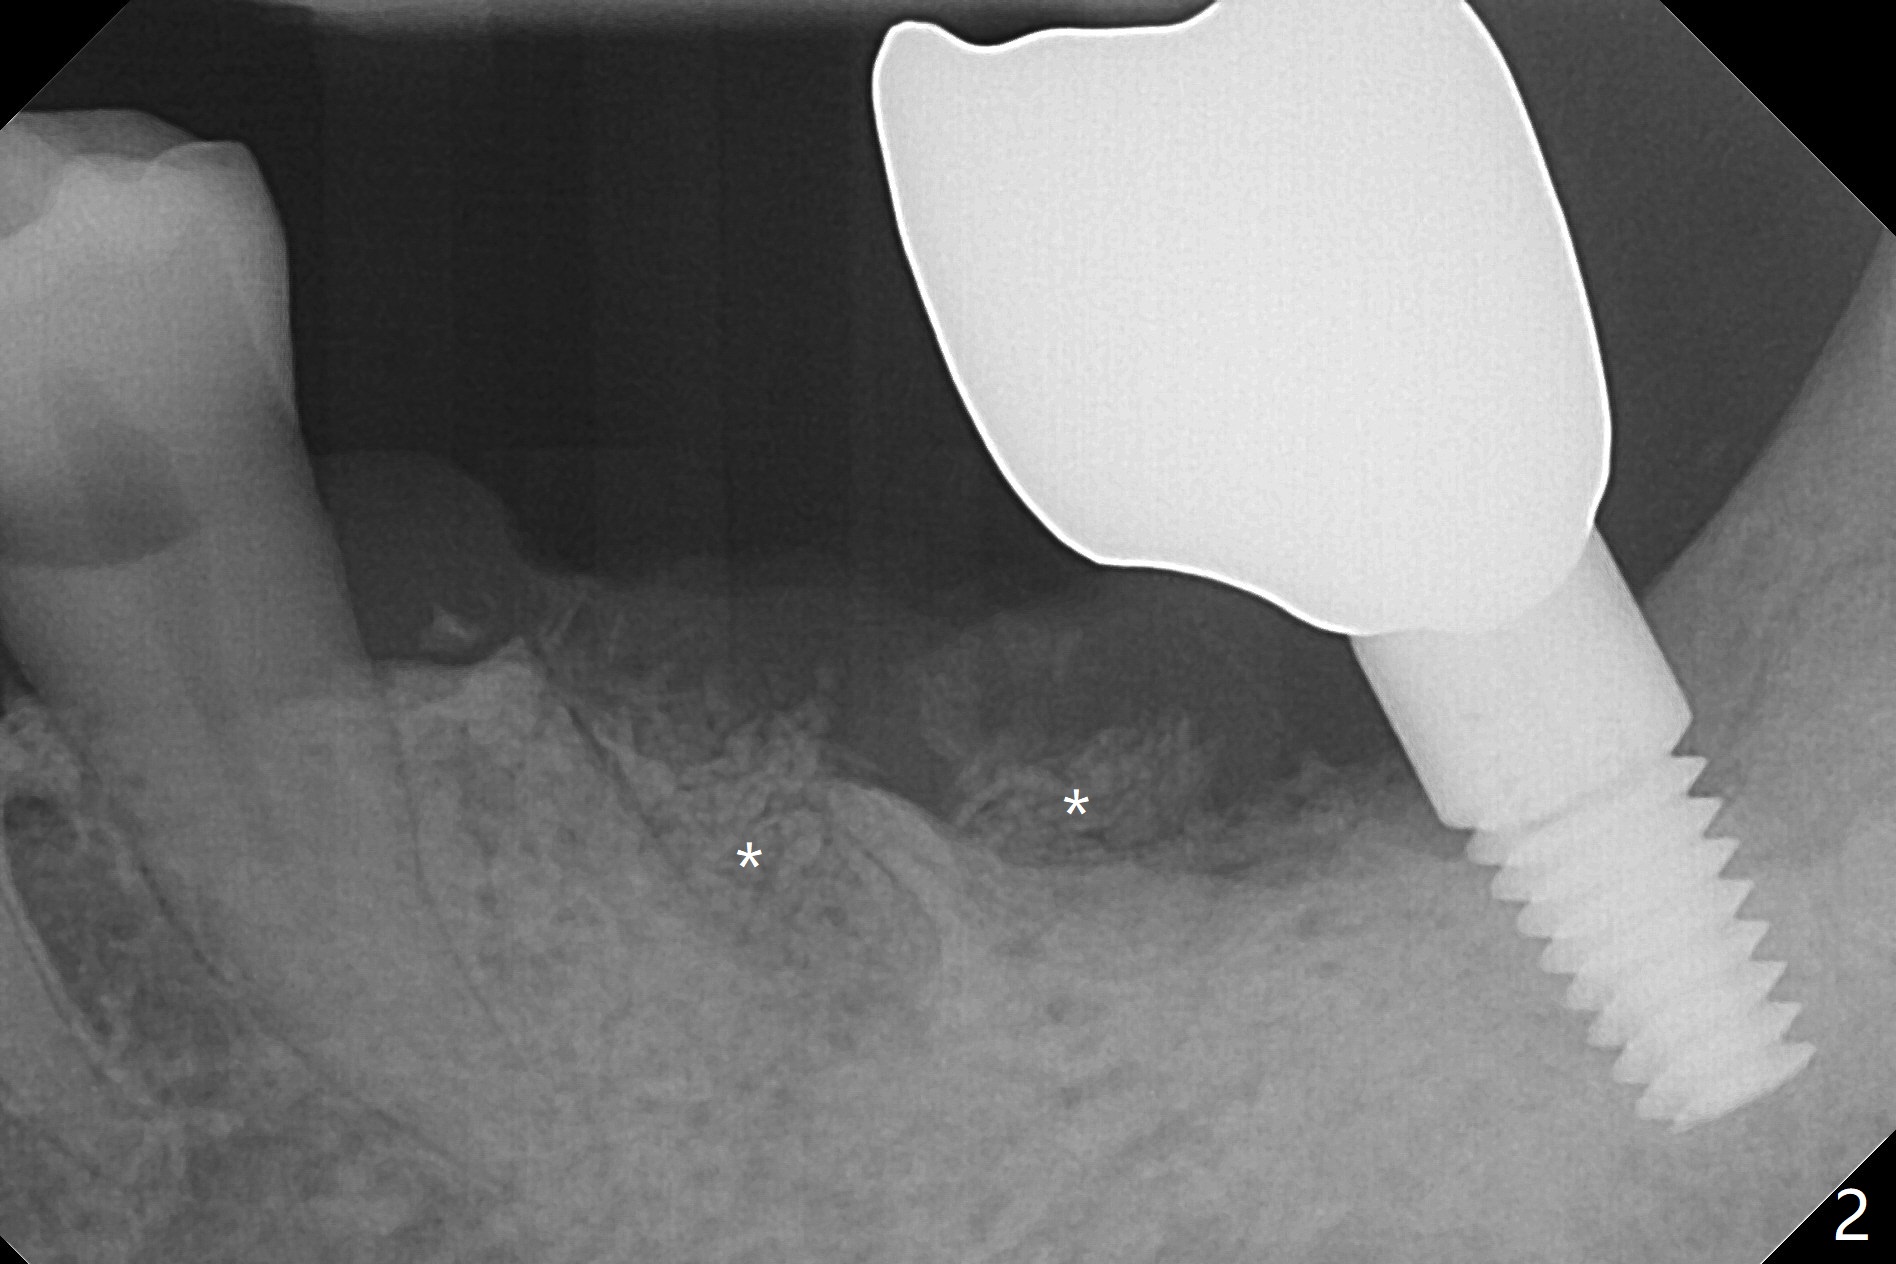

A 66-year-old man develops severe pain at night at #19 seven months post cementation at #18 (Fig.1). There is a piece of the gingiva over the septum, noted after extraction. The mesial and distal sockets are small, being able to hold Vanilla allograft (Fig.2 *), followed by pieces of Collagen plug and suture.